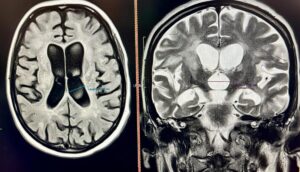

40-річна Соломія не могла самостійно дихати, їсти, розмовляти та ходити. Саме у такому стані вона потрапила у приймальне відділення Університетської лікарні. З 2018 року Соломія страждає на розсіяний склероз, але жодного разу не лікувала це захворювання. Коли вона вже була без свідомості, мама викликала “швидку”

Замість Соломії дихав апарат ШВЛ, замість повноцінної їжі вона отримувала спеціальне харчування через назогастральний зонд. Крім неврологічних проблем, у пацієнтки діагностували важке токсичне ураження печінки, тромбоемболію легеневих артерій, тромбофлебіт (запалення стінок вен і формування тромбу у судині) у нозі і запалення вуха.

Жінка пройшла курс спеціалізованого лікування, в тому числі пульс-терапію.

«Частина змін для Соломії незворотні, але вона ми отримали добрий результат. Після реабілітації пацієнтка зможе ходити і обслуговувати себе сама, супутні патології ми також пролікували, тож вона почувається значно краще. Далі вона отримуватиме хворобомодифікуючу терапію, яка зможе зупинити прогресування хвороби”, – пояснила Мар’яна Бойчук, завідуюча неврологічного відділення.